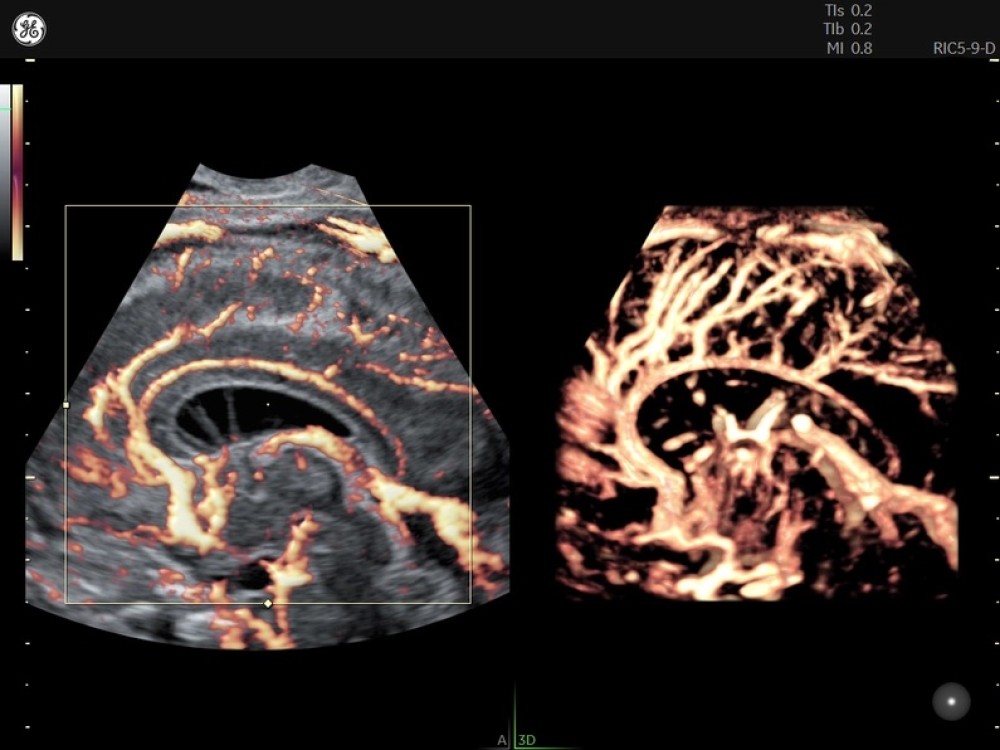

• Voluson Expert 22 real vaxtda yüksək məkan həssaslığına malik görüntülərin əldə olunmasını təmin edən avansert 4D volumetrik görüntüləmə texnologiyasından istifadə edir və bu, klinik diaqnostikanın dəqiqliyini əhəmiyyətli dərəcədə artırır.

• 3D/4D volumetrik görüntüləmə

• HDlive Studio+ (avansert render texnologiyası)

• Endokavitar Volumetrik Prob RIC5-9-D

• Endokavitar Volumetrik Prob RIC10-D

• Endokavitar Volumetrik Prob RIC6-12-D